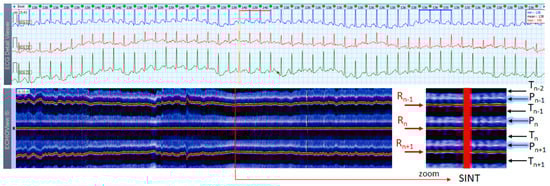

Figure 7. A 3-lead Holter ECG strip (22 s, 25 mm/s) and ECHOView image (ECG lead 1, height = 1500 ms, width resolution = 80 beats/25 mm) of a 21-year old female patient with SINT. The two pages (ECG—top and ECHOView—bottom) are aligned with vertical lines in the highest rate SINT (max HR = 158 bpm read from instant HR values above each QRS complex in the ECG page). In ECG, the atypical morphology of the P-wave (narrow-based, tall, and sharp) and its superimposition on the previous T-wave requires differentiation from an atrial tachycardia. In ECHOView (original and zoomed), the P-wave is a visible blue-white horizontal band (Pn), preceding the red R-wave line (Rn), which confirms the sinus rhythm. ECHOView color map: Yellow-white trace (P-wave of the atrial depolarization, Pn: current, Pn+1, Pn+2: 2 next, Pn−1: previous); Red traces (R-peak of ventricular depolarization, Rn: current, Rn+1: next, Rn−1: previous); Blue-white traces (T-wave of ventricular repolarization, Tn: current, Tn+1: next, Tn−1, Tn−2: 2 previous). SINT—sinus tachycardia.

Jcdd 10 00360 g007

Figure 8. A 3-lead Holter ECG strip (22 s, 25 mm/s) and ECHOView image (ECG lead 1, height = 1500 ms, width resolution = 80 beats/25 mm) of a 38-year old male patient with SINT. The two pages (ECG—top and ECHOView—bottom) are aligned with vertical lines in the highest rate SINT (max HR = 148 bpm read from instant HR values above each QRS complex in the ECG page). In ECG, the atrial depolarization before the R wave is barely visible in the ECG channels and differentiation of SINT from AVNRT in this case is difficult. In ECHOView (original and zoomed), the P-wave is a visible white horizontal band (Pn), preceding the red R-wave line (Rn), which confirms the sinus rhythm. ECHOView color map: Blue-white traces (P-wave of atrial depolarization, Pn: current, Pn+1: next, Pn−1: previous); Red traces (R-peak of ventricular depolarization, Rn: current, Rn+1: next, Rn−1: previous); Black traces (T-wave of ventricular repolarization, Tn: current, Tn+1: next, Tn−1, Tn−2: 2 previous). SINT—sinus tachycardia, AVNRT—atrio-ventricular nodal reentrant tachycardia, AFL—atrial flutter.

Jcdd 10 00360 g008